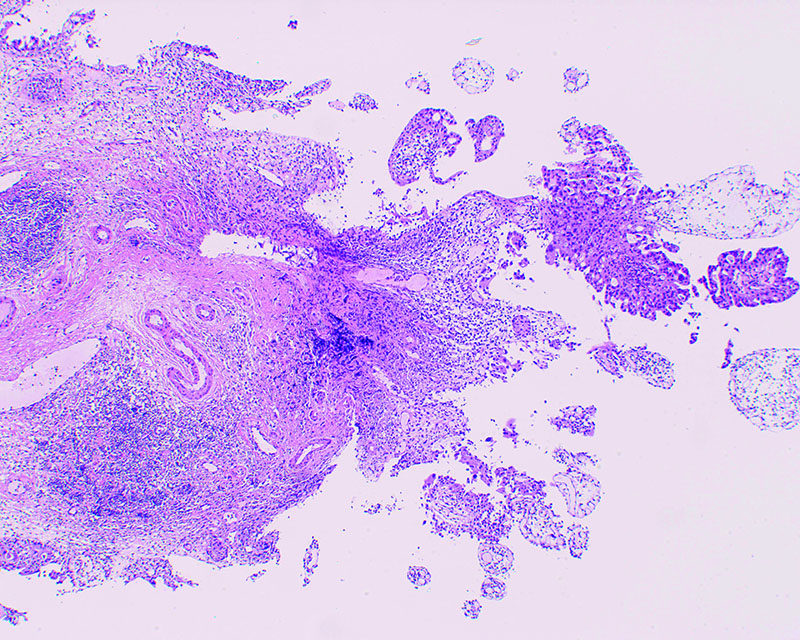

病理 SCC>UC, pT1, High grade

コメント

一部潰瘍化のみられる結節型腫瘍。NBIにて腫瘍辺縁が分かりやすくなる。